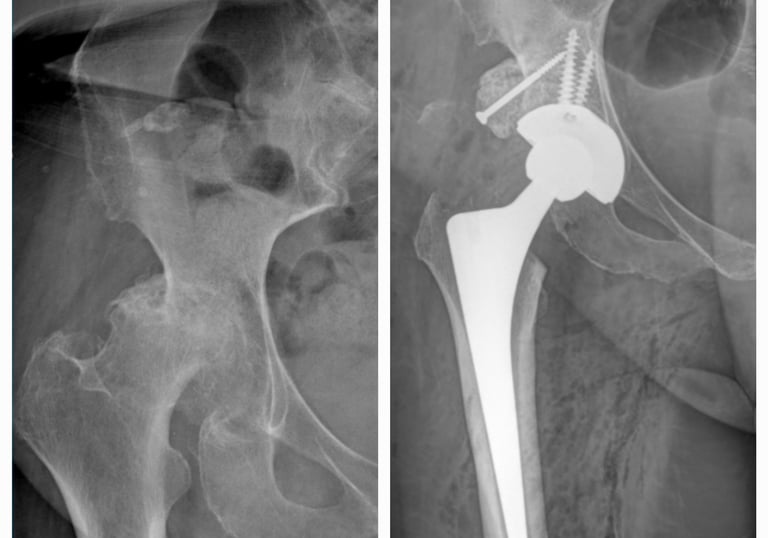

Displasia del desarrollo de cadera: es una alteración en la formación de la articulación de la cadera que está presente desde el nacimiento. Puede provocar que la cabeza del fémur no encaje bien en el acetábulo (la cavidad de la pelvis), lo que con el tiempo ocasiona dolor, cojera y desgaste temprano de la articulación. Su detección y tratamiento oportuno permiten prevenir complicaciones y preservar la función de la cadera.

Secuelas de displasia de cadera

Cirugía en la que se reemplaza la articulación dañada por una prótesis nueva. Se realiza en casos de desgaste severo, artrosis o lesiones que provocan dolor intenso y limitan la movilidad. El objetivo es devolver la capacidad de caminar, realizar actividades cotidianas sin dolor y mejorar la calidad de vida.

Prótesis de cadera y rodilla